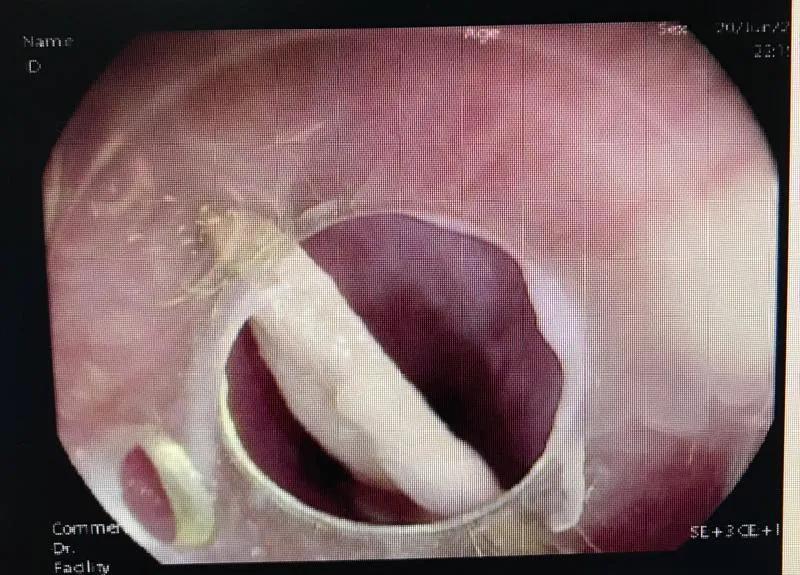

横插在食道内的片状鸭头骨。

三角形的尖锐片状鸭头骨刺入食管壁,并有渗血,稍有不慎极有可能造成患者食管穿孔,大血管出血。6月20日晚,吉林市人民医院消化中心经过多学科会诊讨论,选择急诊内镜超级微创手术,成功将这片鸭头骨取出,避免了患者开胸手术。